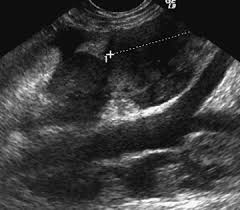

![]() |

| Linfonodo ilíaco medial normal. |